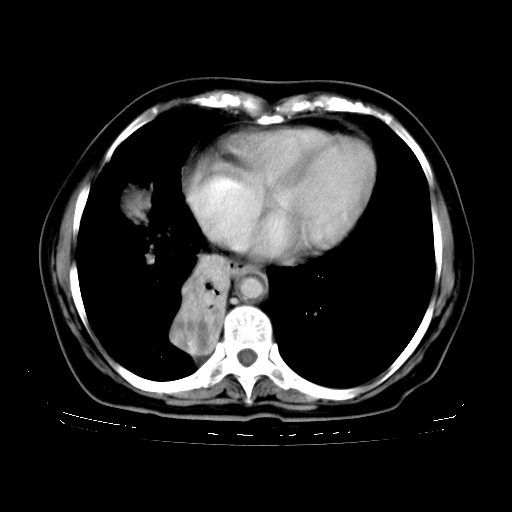

标题: CT23067:女,70岁,咳嗽、咳痰一个月,低热一周。 [打印本页]

女,70岁,咳嗽、咳痰一个月,低热一周。

1、右肺占位,考虑周围型ca 。

2、右下肺软组织密度肿块影,考虑肺隔离征。

3、两肺肺结核(右肺下叶背段及左肺)。

4、主动脉夹层。

5、右侧少量胸腔积液。